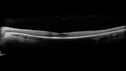

RP_rarei_071519_02.png

Retinitis Pigmentosa - Simplex - 16 year old female good vision364 viewsDifficulty with night vision

No family history

VA 20/25 OD, 20/16 OS

Negative for RPE65